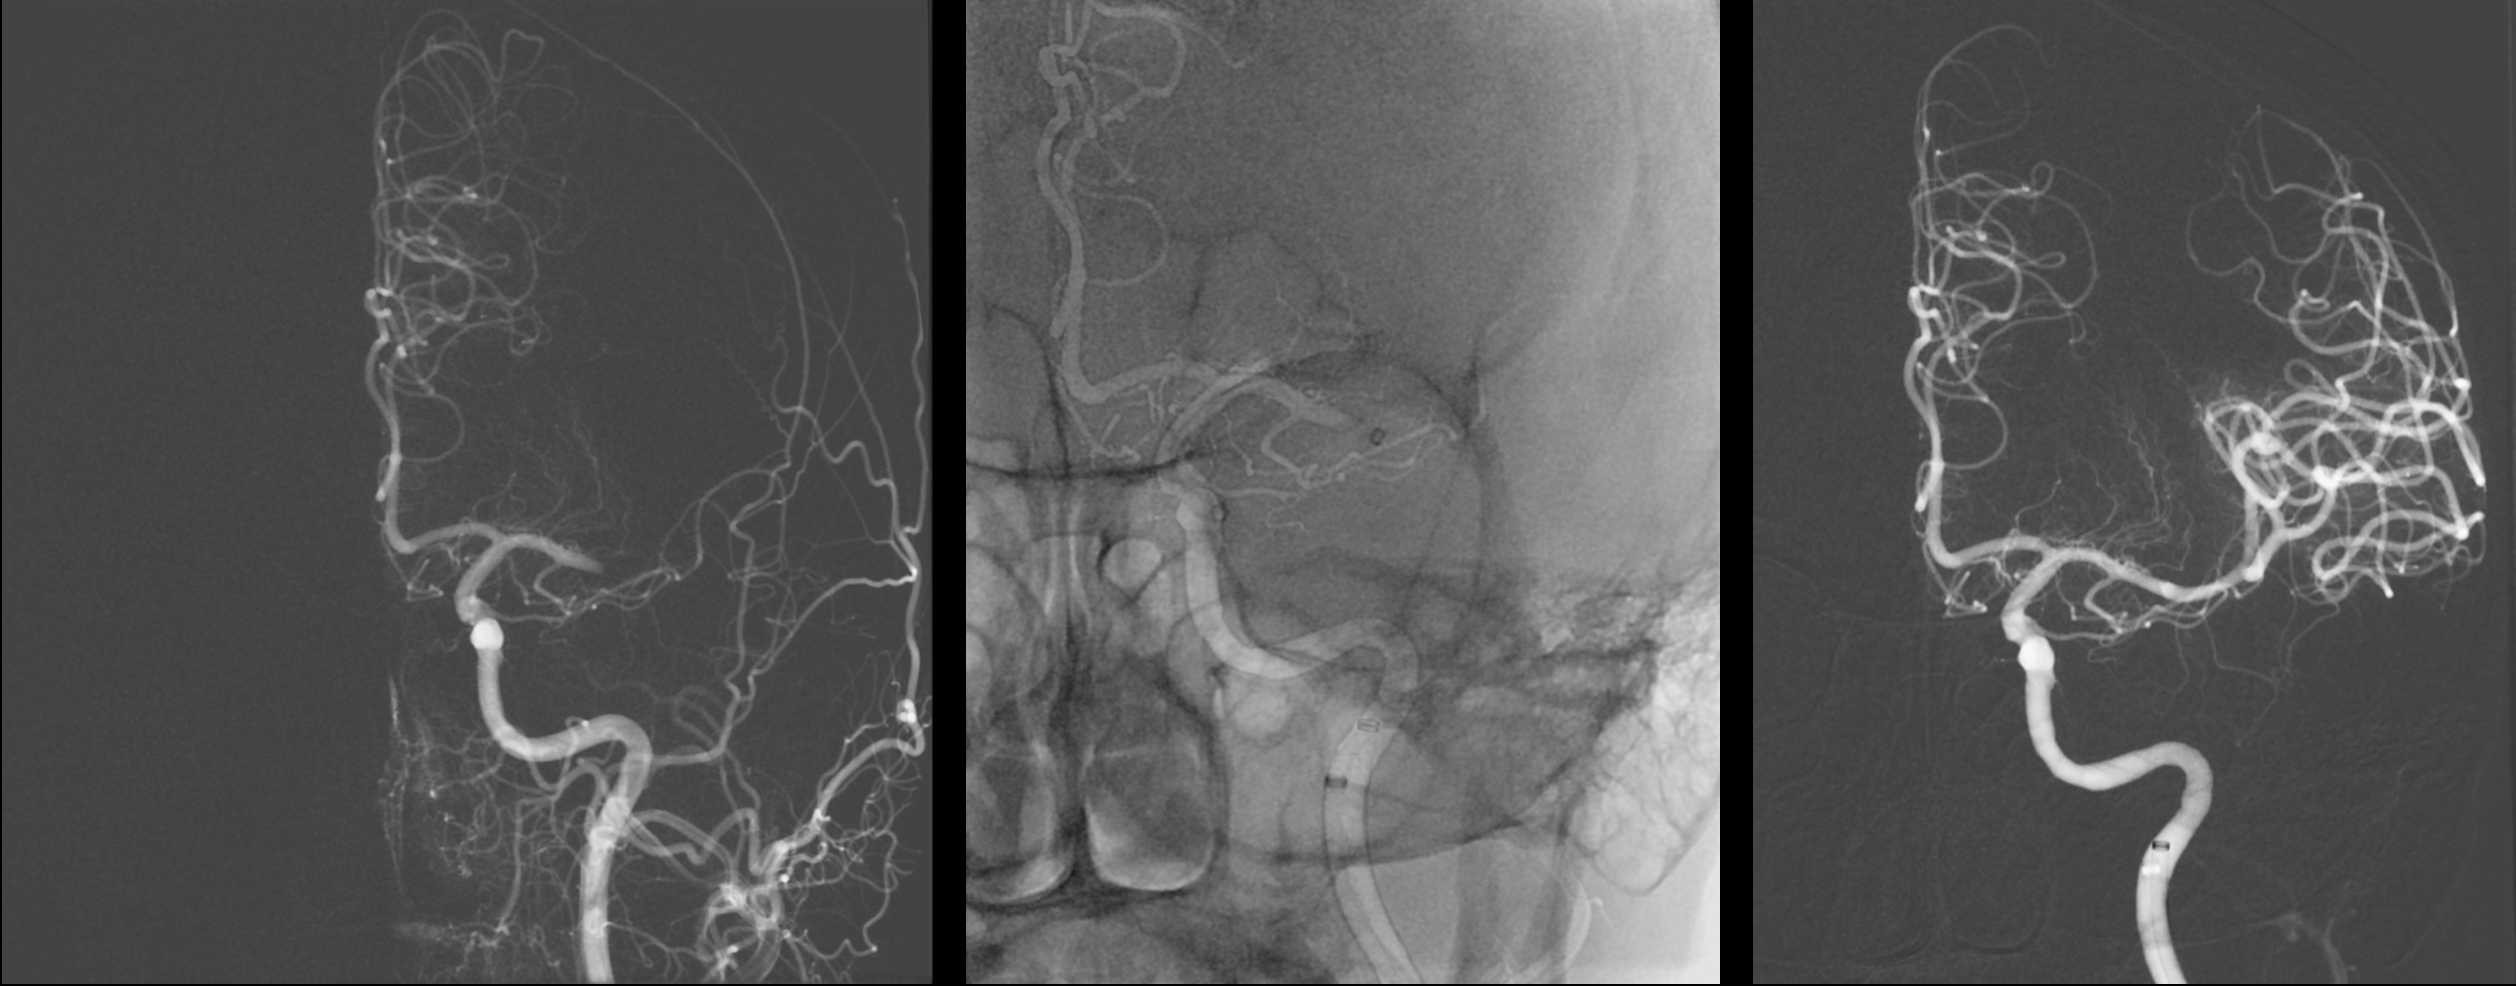

na pracovištích Kliniky zobrazovacích metod provádíme diagnostiku a také léčbu mozkové ischémie – mozkové mrtvice. Protože její výsledek je závislý na včasném zahájení léčby, přivolejte pomoc okamžitě osobě, která náhle přestala mluvit, nebo hýbat pravou nebo levou polovinou těla. Na urgentním příjmu FN Plzeň provedeme vyšetření výpočetní tomografií pomocí výpočetní tomografie, vyloučíme, že nejde o krvácení, posoudíme životaschopnost mozkové tkáně perfidním vyšetřením a zobrazíme cévy zásobující mozek CT angiografií. Následně za asistence anesteziologů provedeme zavedení speciálního nástroje do tepenného řečiště přes stehenní tepnu. Nástroj zavedeme až do mozkové cévy, ze které odstraníme krvení sraženinu a obnovíme průtok do postižené oblasti mozku. Čím dříve se tok krve obnoví tím méně odumře nervových buněk mozku – neuronů a tím je menší výsledné postižení mozkových funkcí. PAMATUJTE ČAS JE MOZEK